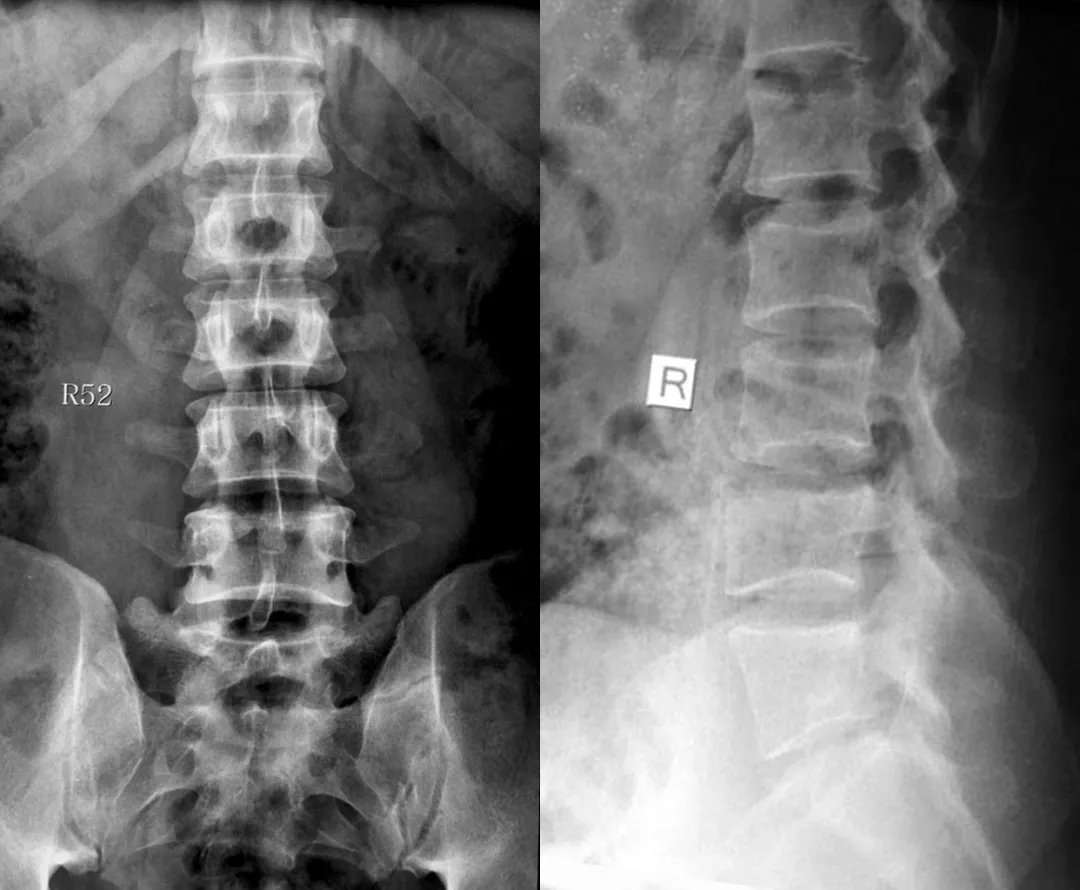

- 影像学检查:如X光、CT扫描或MRI,可以帮助医生观察脊柱和关节的异常。